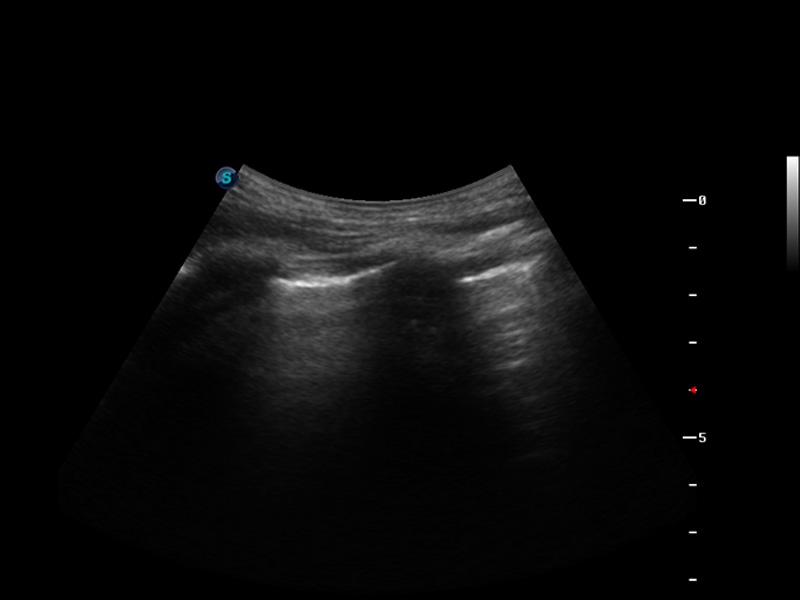

S9便携式彩色多普勒超声诊断仪是狗万官方网站研发的高端便携彩超设备,外观设计新颖、产品性能卓越。S9在便携超声领域采用了突破传统的触摸屏交互设计,并以先进的软件硬件技术和设计理念,为您带来清晰的图像质量、稳定的工作性能和便捷的操作体验。

μ-Scan微米成像